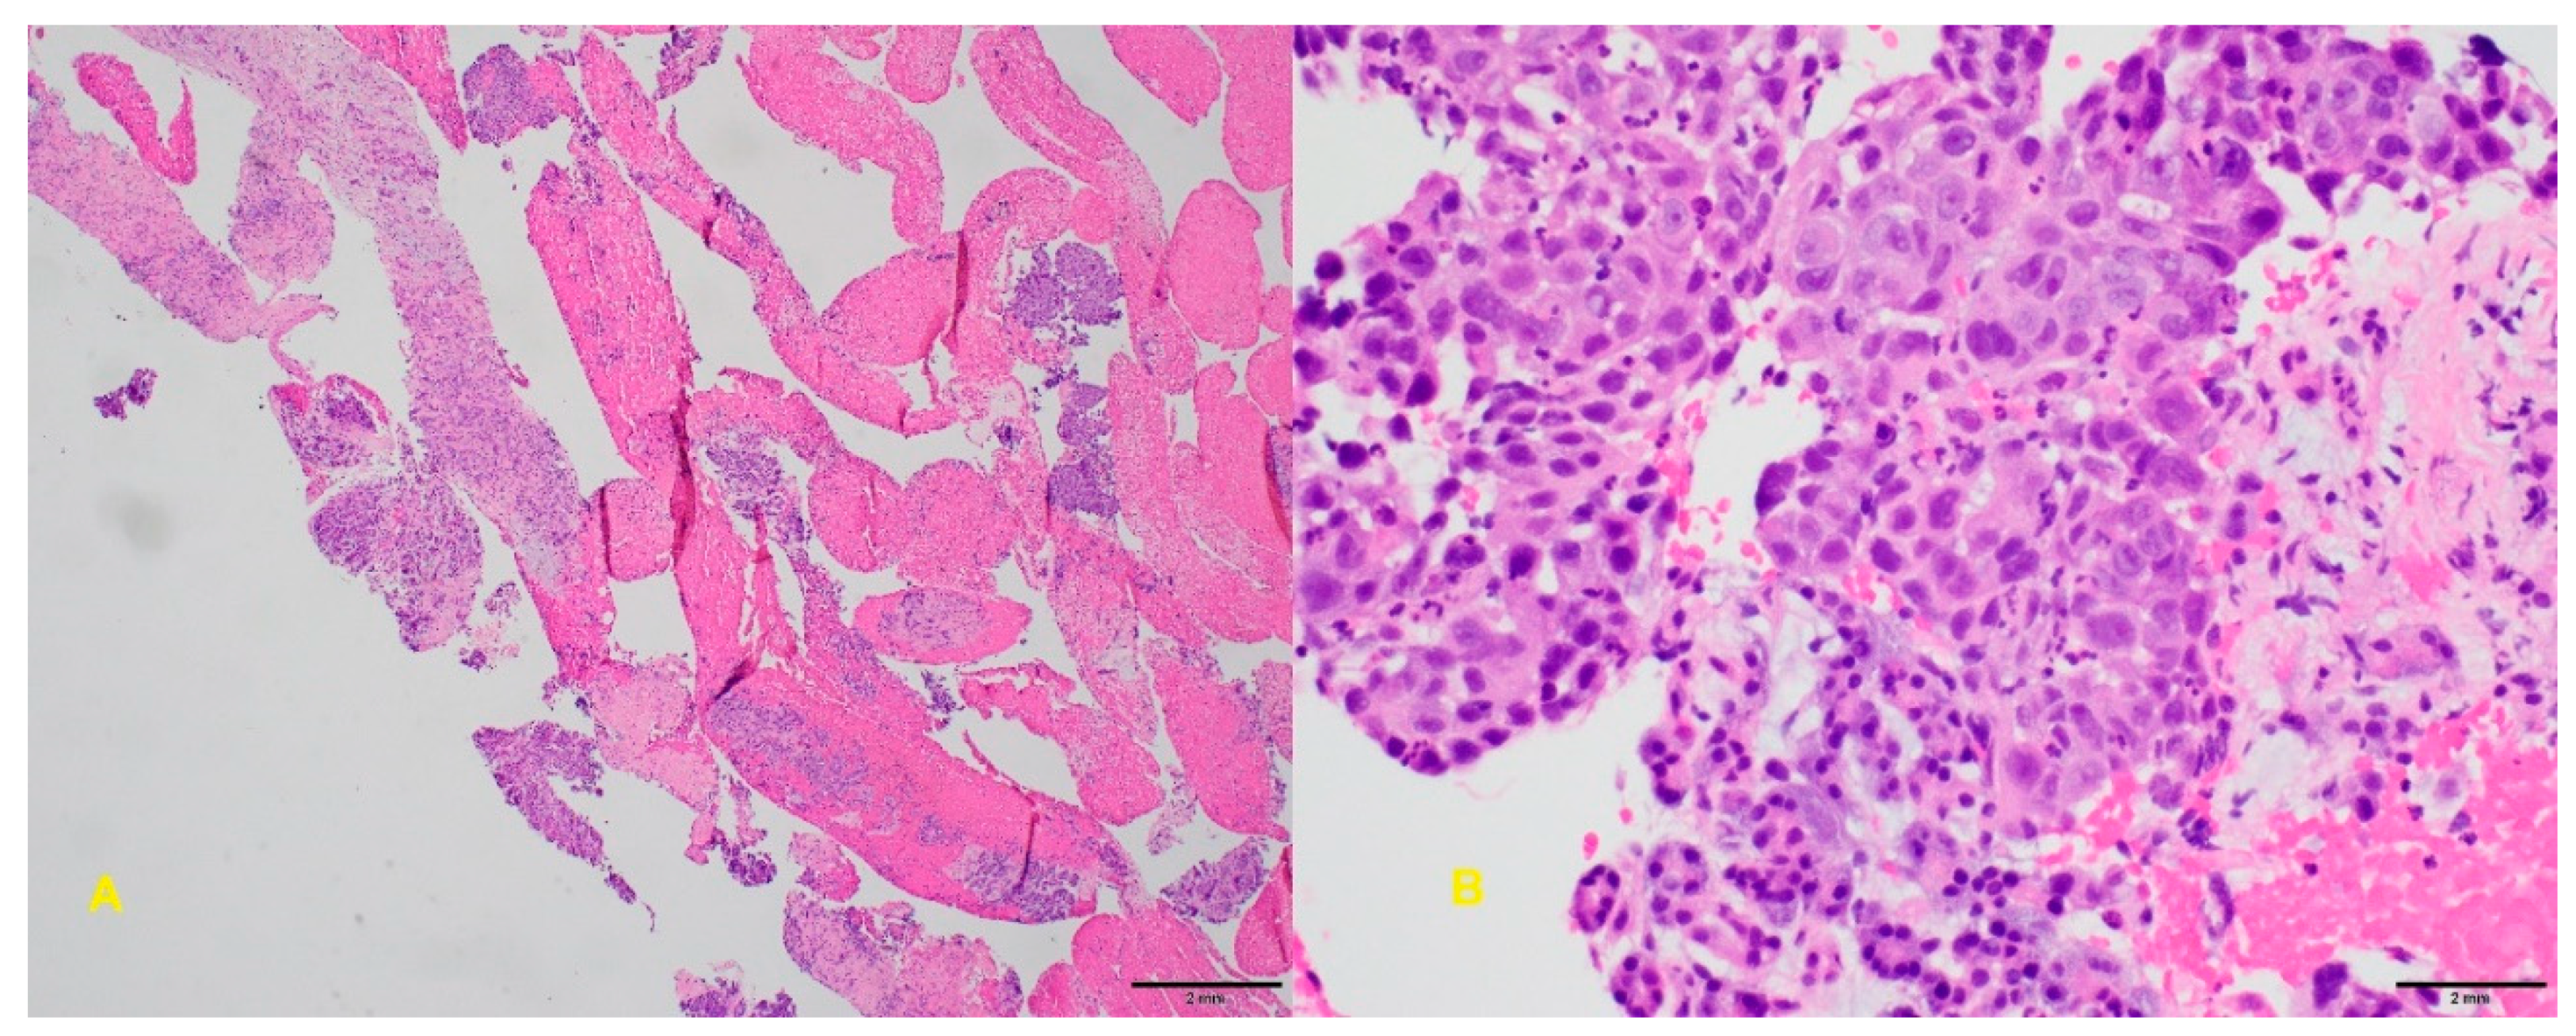

6.4. Endoscopic Ultrasound-Guided Fine-Needle Biopsy

- Ayres, L.R.; Kmiotek, E.K.; Lam, E.; Telford, J.J. A comparison of endoscopic ultrasound-guided fine-needle aspiration and fine-needle biopsy in the diagnosis of solid pancreatic lesions. Can. J. Gastroenterol. Hepatol. 2018, 2018, 1–6. [Google Scholar] [CrossRef]

- Van Riet, P.A.; Larghi, A.; Attili, F.; Rindi, G.; Nguyen, N.Q.; Ruszkiewicz, A.; Kitano, M.; Chikugo, T.; Aslanian, H.; Farrell, J. A multicenter randomized trial comparing a 25-gauge EUS fine-needle aspiration device with a 20-gauge EUS fine-needle biopsy device. Gastrointest. Endosc. 2019, 89, 329–339. [Google Scholar] [CrossRef]

- Asokkumar, R.; Ka, C.Y.; Loh, T.; Ling, L.K.; San, T.G.; Ying, H.; Tan, D.; Khor, C.; Lim, T.; Soetikno, R. Comparison of tissue and molecular yield between fine-needle biopsy (FNB) and fine-needle aspiration (FNA): A randomized study. Endosc. Int. Open 2019, 7, E955–E963. [Google Scholar] [CrossRef]

- Facciorusso, A.; Bajwa, H.S.; Menon, K.; Buccino, V.R.; Muscatiello, N. Comparison between 22G aspiration and 22G biopsy needles for EUS-guided sampling of pancreatic lesions: A meta-analysis. Endosc Ultrasound. 2019, 10. [Google Scholar] [CrossRef]

- Khan, M.A.; Grimm, I.S.; Ali, B.; Nollan, R.; Tombazzi, C.; Ismail, M.K.; Baron, T.H. A meta-analysis of endoscopic ultrasound–fine-needle aspiration compared to endoscopic ultrasound–fine-needle biopsy: Diagnostic yield and the value of onsite cytopathological assessment. Endosc. Int. Open 2017, 5, E363–E375. [Google Scholar] [CrossRef]